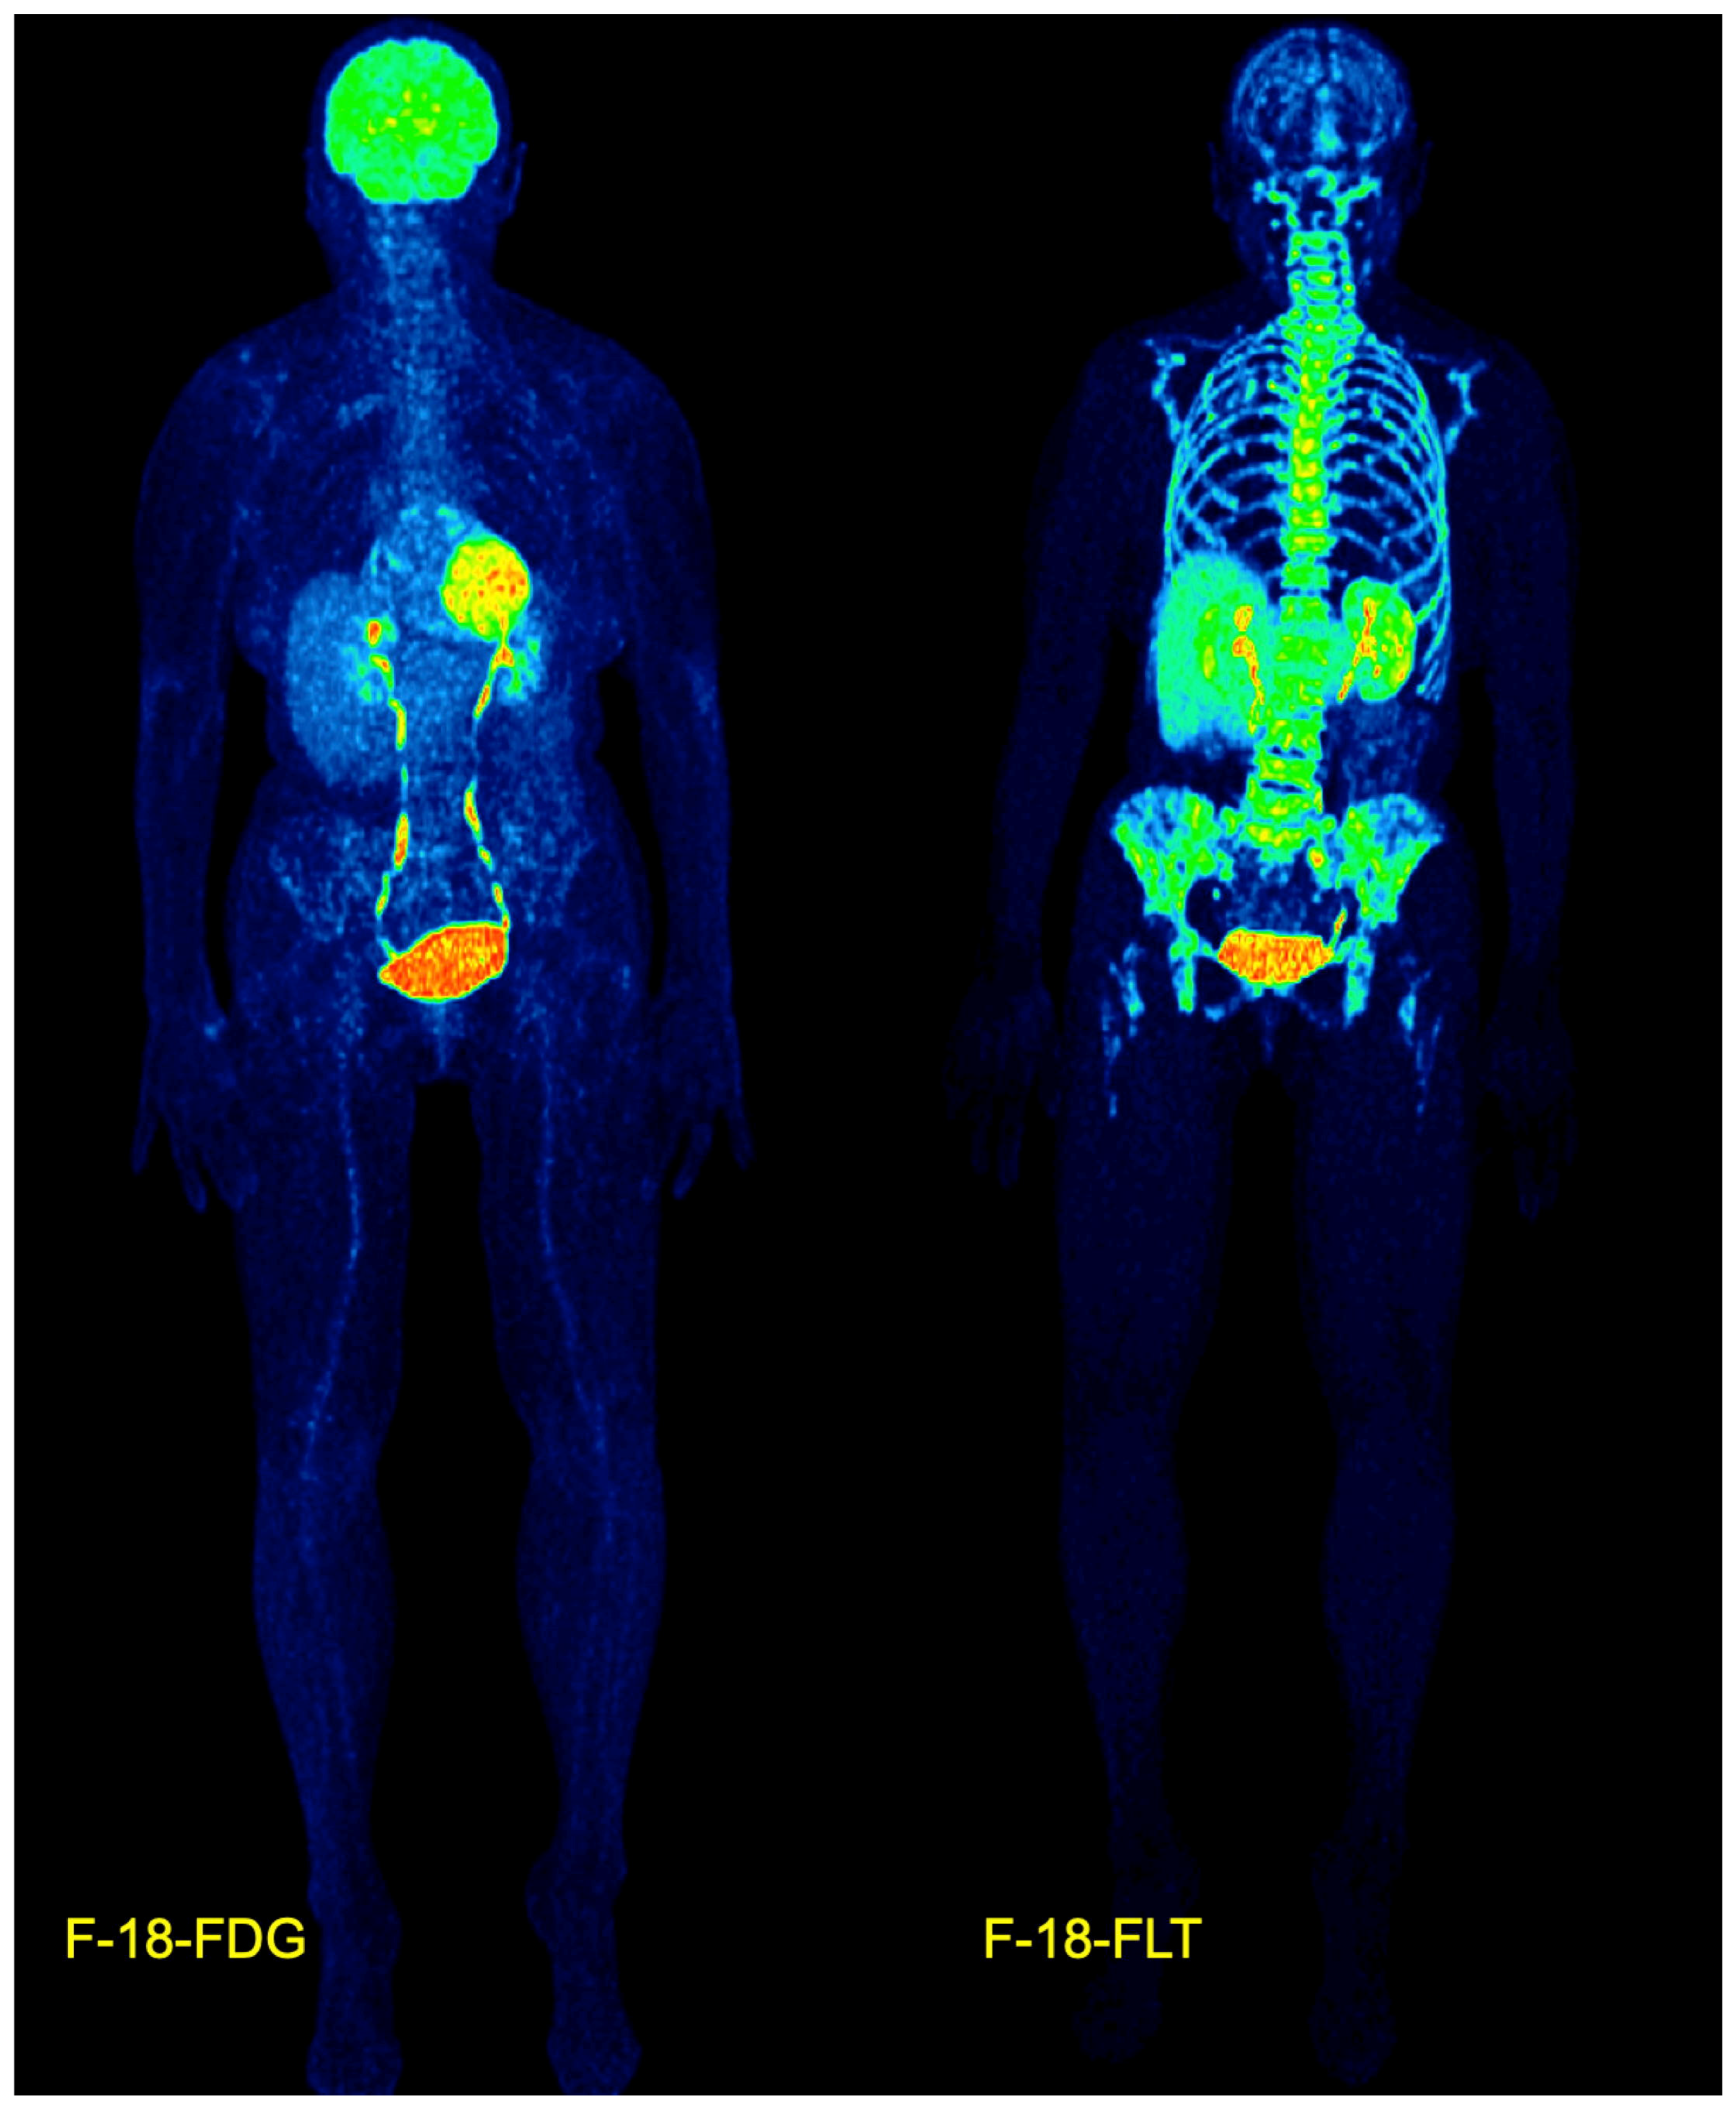

- Sachpekidis, C.; Goldschmidt, H.; Kopka, K.; Kopp-Schneider, A.; Dimitrakopoulou-Strauss, A. Assessment of glucose metabolism and cellular proliferation in multiple myeloma: A first report on combined 18F-FDG and 18F-FLT PET/CT imaging. EJNMMI Res. 2018, 8, 28. [Google Scholar] [CrossRef]